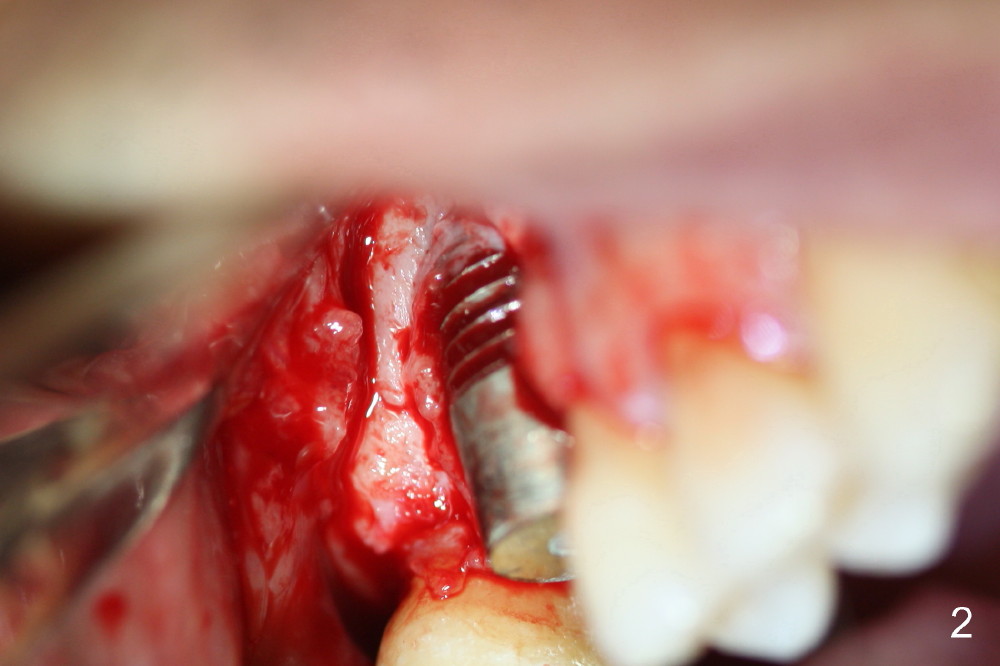

A fistula forms 3 months postop, buccal to the implant at the site of #3 (Fig.1 <). There are 2 possible reasons. First the implant was placed too buccally due to palatal root exposure before extraction. Second, the patient could not tolerate oral Amoxicillin. It is most likely that the buccal implant threads are not covered by the bone. Bone graft is required.

First, Clindamycin should be taken with Chlorhexidine mouth rinse 2 days prior to surgery. After incision (dashed line in Fig.1), the exposed threads are thoroughly irrigated, soaked with Clindamycin guaze 3 times, and treated with Perfogel and Endogain. Following allograft/Osteoten placement, Osteotape is used to cover the graft. Osteotape is a special collagen membrane with Osteogen already incorporated.